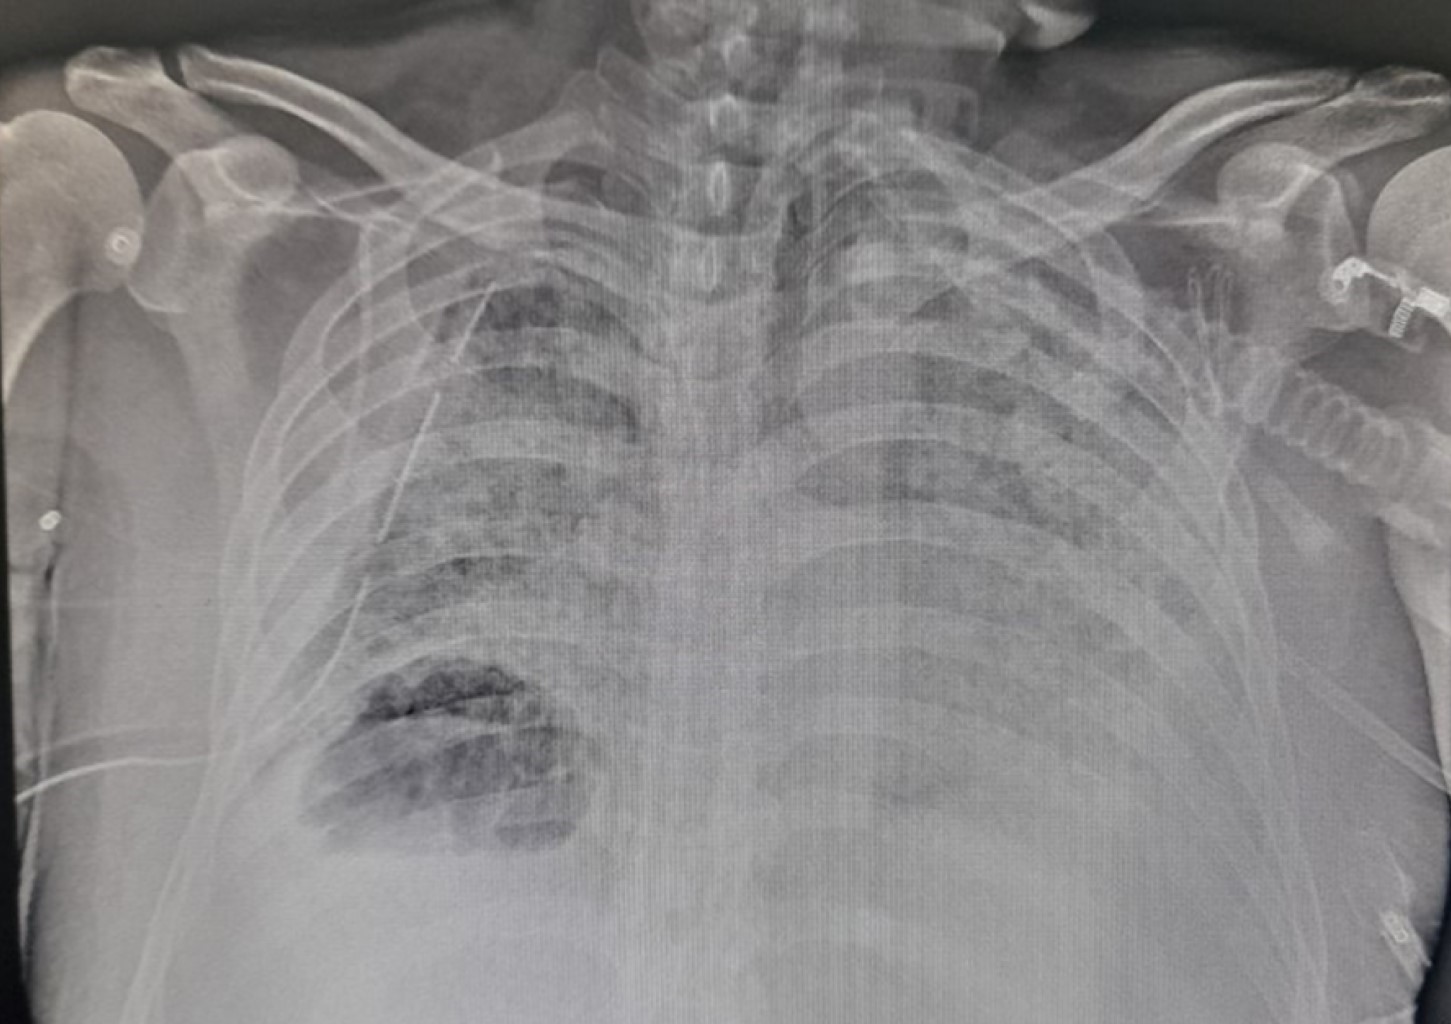

Se decide colocar sonda endopleural en quinto espacio intercostal en su intersección con la línea axilar media derecha obteniendo 200 mL de material serohemático, se conecta a succión continua, se verifica colocación de sonda endopleural con control radiográfico posterior (Figura 3). Se solicita valoración por el servicio cirugía de tórax, quien indica manejo conservador con seguimiento a través de estudios de imagen. Se retira la sonda endopleural a los 10 días de colocada, corroborando expansión pulmonar (Figura 4). Se logra el retiro de la ventilación a los 68 días de iniciado el cuadro y 58 días de ventilación mecánica tolerando de manera adecuada, siendo egresado a sala general para continuar con su manejo.

Figura 3